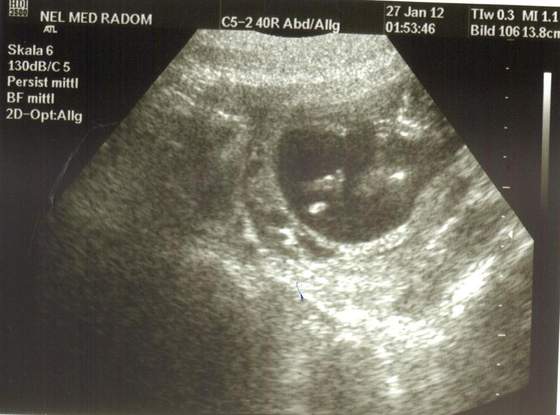

20120131_094123.jpg Pochwale się nowym zdjęciem. Troche niewyraźne ale widać jak maluch ssie kciuka :)

milejdi uroczy widok !!!!!!!!!!!!!!!!!!!!!!! :)

Zobacz załącznik 431877 Pochwale się nowym zdjęciem. Troche niewyraźne ale widać jak maluch ssie kciuka :)

slodkie :) malutkie nasze cuda :)